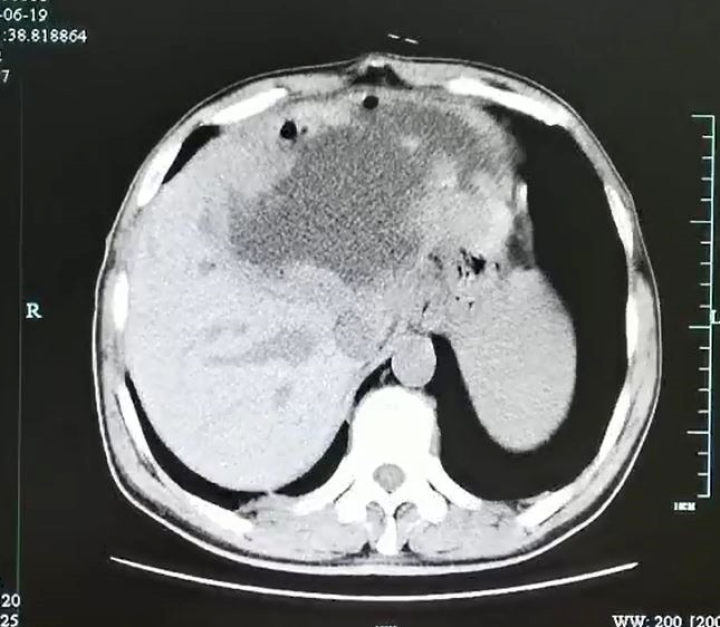

男子左肝被"掏空",体内取出虫卵!医生:你还敢这样吃鱼吗?

图片尺寸720x627